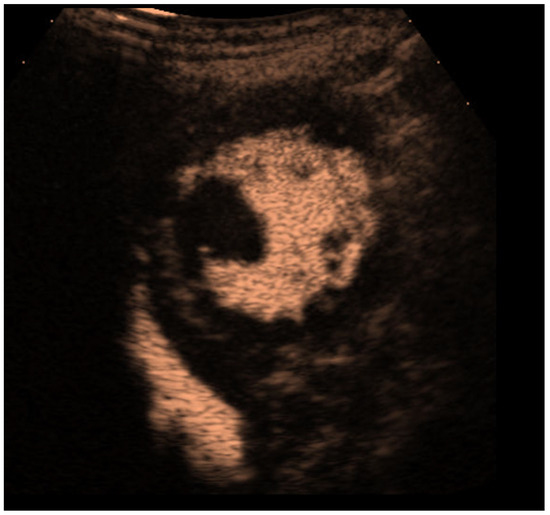

| Imaging method | start with low-MI-contrast-specific imaging for assessment of global and regional LV function then use intermediate-MI-contrast-specific imaging which provides better display of LV trabeculations |

| Imaging planes | standard apical views parasternal and apical short-axis view |

| Contrast application | bolus injection |

| Typical findings | trabeculated layer apical, lateral, and inferior: more than 3 trabeculations, ratio of trabeculated/compact myocardium >2 The number of trabeculations and the ratio of trabeculated/compact myocardium does not seem to impact clinical management |

| Alternative imaging | MRI for tissue characterization in dilated cardiomyopathy and risk assessment in hypertrophic cardiomyopathy, assessment of LV thrombi when CEUS recordings are non-diagnostic |